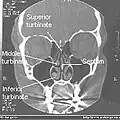

Normal Nose CT Front cross section -